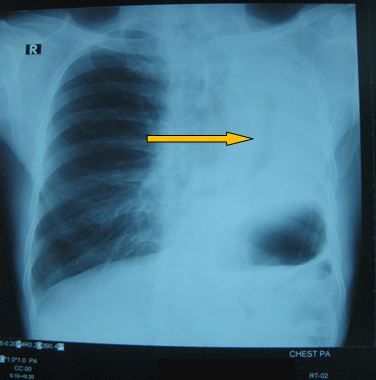

-          X- Quang tim phổi thẳng có hình ảnh đám mờ toàn bộ thùy trên phổi trái:

Trước điều trị

Tổn thương đám mờ toàn bộ vị trí thuỳ trên phổi trái